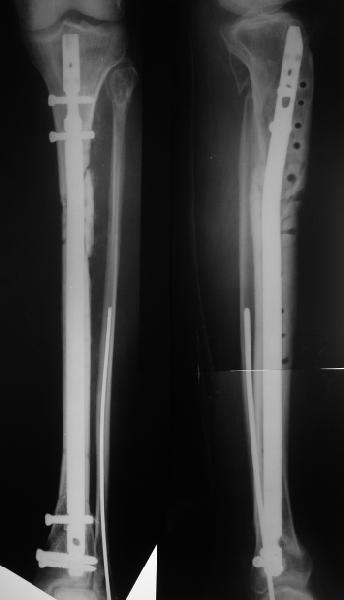

Декабрь 2003

22 июня 2004

Еще раз спасибо! Сделали вчера. Все прошло по плану, интраоперационное фото после удаления пластинки и итоговые снимки прилагаю. Гвоздь бесканальный 12 мм. Сегодня пациентка уже ходит по палате с одним костылем.